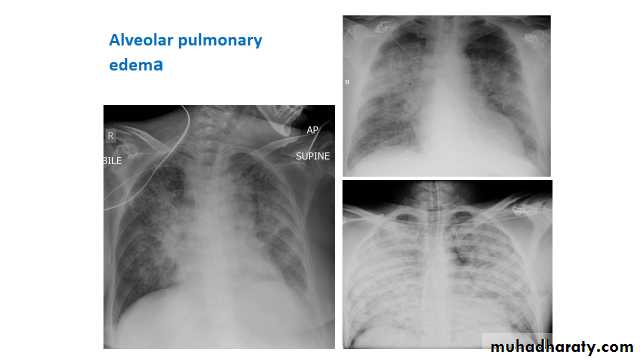

pulmonary alveolar oedema

Pulmonary edema is a broad descriptive term and is usually defined as an abnormal accumulation of fluid in the extra-vascular compartments of the lung .

radiograph include if pressure > 25 mmHg the findings of :

cardiac size/cardio-thoracic ratio: useful for assessing for an underlying cardiogenic cause or associationbat wing pulmonary opacities

presence of HYPERLINK "http://radiopaedia.org/articles/peri-bronchial-cuffing-2" peri-bronchial cuffing

septal lines: HYPERLINK "http://radiopaedia.org/articles/septal-lines-in-lung" Kerley lines become more prominent

pleural effusions

pulmonary venous engorgement/pulmonary blood flow distributionupper lobe pulmonary venous diversion